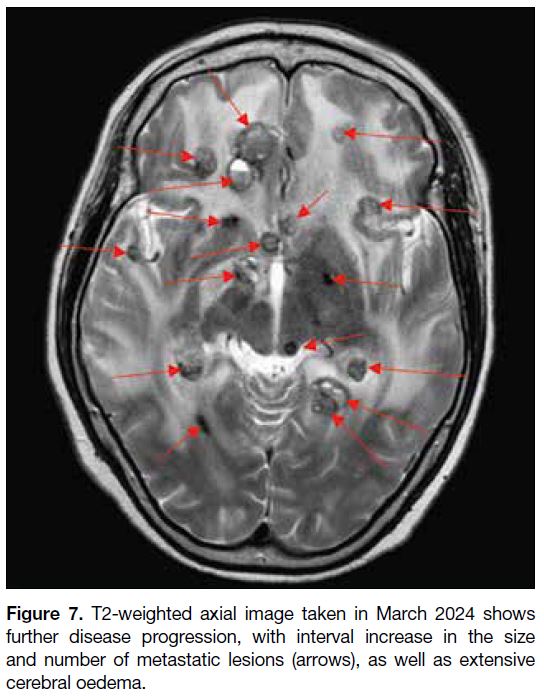

primary within the brain. Postoperatively, the patient

underwent further follow-up MRI scans that revealed

new suspicious drop metastasis at the C4 level, as well as significant progression of brain metastases and

worsening vasogenic oedema (Figure 7). The patient

Figure 7. T2-weighted axial image taken in March 2024 shows

further disease progression, with interval increase in the size

and number of metastatic lesions (arrows), as well as extensive

cerebral oedema.